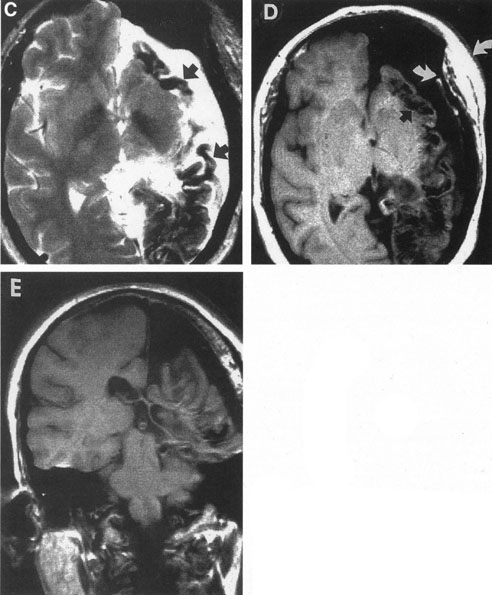

The detection of intracranial AVMs is facilitated by CT scanning and MRI (Fig. 10),88 but optimal management requires selective angiography89 that assesses the size and configuration of the mass, the number and location of feeding arteries, the flow characteristics and degree of steal from brain parenchyma, and the pattern of venous drainage.

Fig. 10. Neuroimaging of arteriovenous malformation. A: Coronal magnetic resonance imaging (MRI) (TR, 600 ms; TE, 20 ms) shows wedge-shaped vascular mass extending from the surface of the parietal cortex (white arrows) to the lateral ventricle (black arrows; asterisk, arterial feeder). B: Posteroanterior left arteriogram of the same lesion. C: Axial computed tomography scan with contrast enhancement. D: Axial MRI of a large arteriovenous malformation, first echo (TR, 2000 ms; TE, 20 ms). E: Second echo (TR, 2000 ms; TE, 90 ms). (From Smith HJ, Strother CM, Kikuchi Y, et al: MR imaging in the management of supratentorial intracranial AVMS. AJNR Am J Neuroradiol 9:225, 1988.)

The therapy for AVMs has been reviewed elsewhere.91–93 The preferred treatment remains complete surgical excision of the malformation. However, significant advances in endovascular and radiosurgical techniques have resulted in a marked increase in the use of multimodal, staged approaches to AVM treatment. A variety of intravascular techniques use embolization91 with materials such as particles of polyvinyl alcohol (PVA), platinum coils, and injection of liquid N-butyl-cyanoacrylate (NBCA) adhesive (Fig. 11). Complications of intravascular embolotherapy include vessel perforation by the catheter, migration of embolic materials, and infarction and hemorrhage of normal brain.

Fig. 11. Embolization of middle cerebral vessels that supply occipital lobe arteriovenous malformation (AVM). The patient had a subarachnoid and intraparenchymal hemorrhage that produced a left homonymous field defect. A: Right carotid arteriogram demonstrates contribution via posterior communicating artery to a right occipital lobe AVM. B: Vertebral injection. The arrow points to the enlarged right posterior cerebral artery that is a major feeder of the AVM. C: Right carotid arteriogram during glue embolization procedure. The arrow points to a catheter as it traverses the segment seen in (B). The catheter was advanced via the internal carotid artery but is positioned far posteriorly. D: Upper branches to the AVM now are occluded, with residual low-flow vascularization via the middle cerebral artery. E: Skull film showing radiopaque glue within the AVM and blood vessels previously supplying it. The patient had a persistent visual field defect but greatly reduced headache and no persistence of subjective bruit. (Courtesy of Dr. Joseph Horton.)